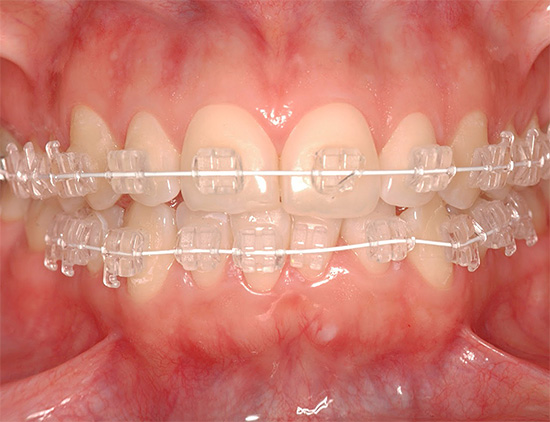

Inoltre, i sistemi di staffe si differenziano per il materiale con cui sono realizzati:

- Bretelle in ceramica - non visibili sui denti, più resistenti di quelle in plastica. Tra gli svantaggi - a causa dell'elevato grado di attrito dell'arco nel castello, il tempo di trattamento totale aumenta. Il costo di tali apparecchi è superiore a quello del metallo e della plastica.

- Bretelle in zaffiro: il più trasparente e invisibile possibile sui denti, ma molto più costoso degli analoghi.